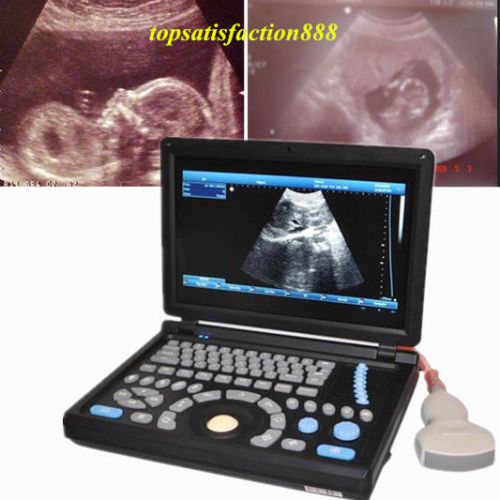

3D PC Digital Laptop 3.5Mhz abdominal Probe +Ultrasound ScannerMachine Main Unit

3D PC Digital Ultrasound ScannerMachine Laptop Main Unit+7.5Mhz Superficia Probe